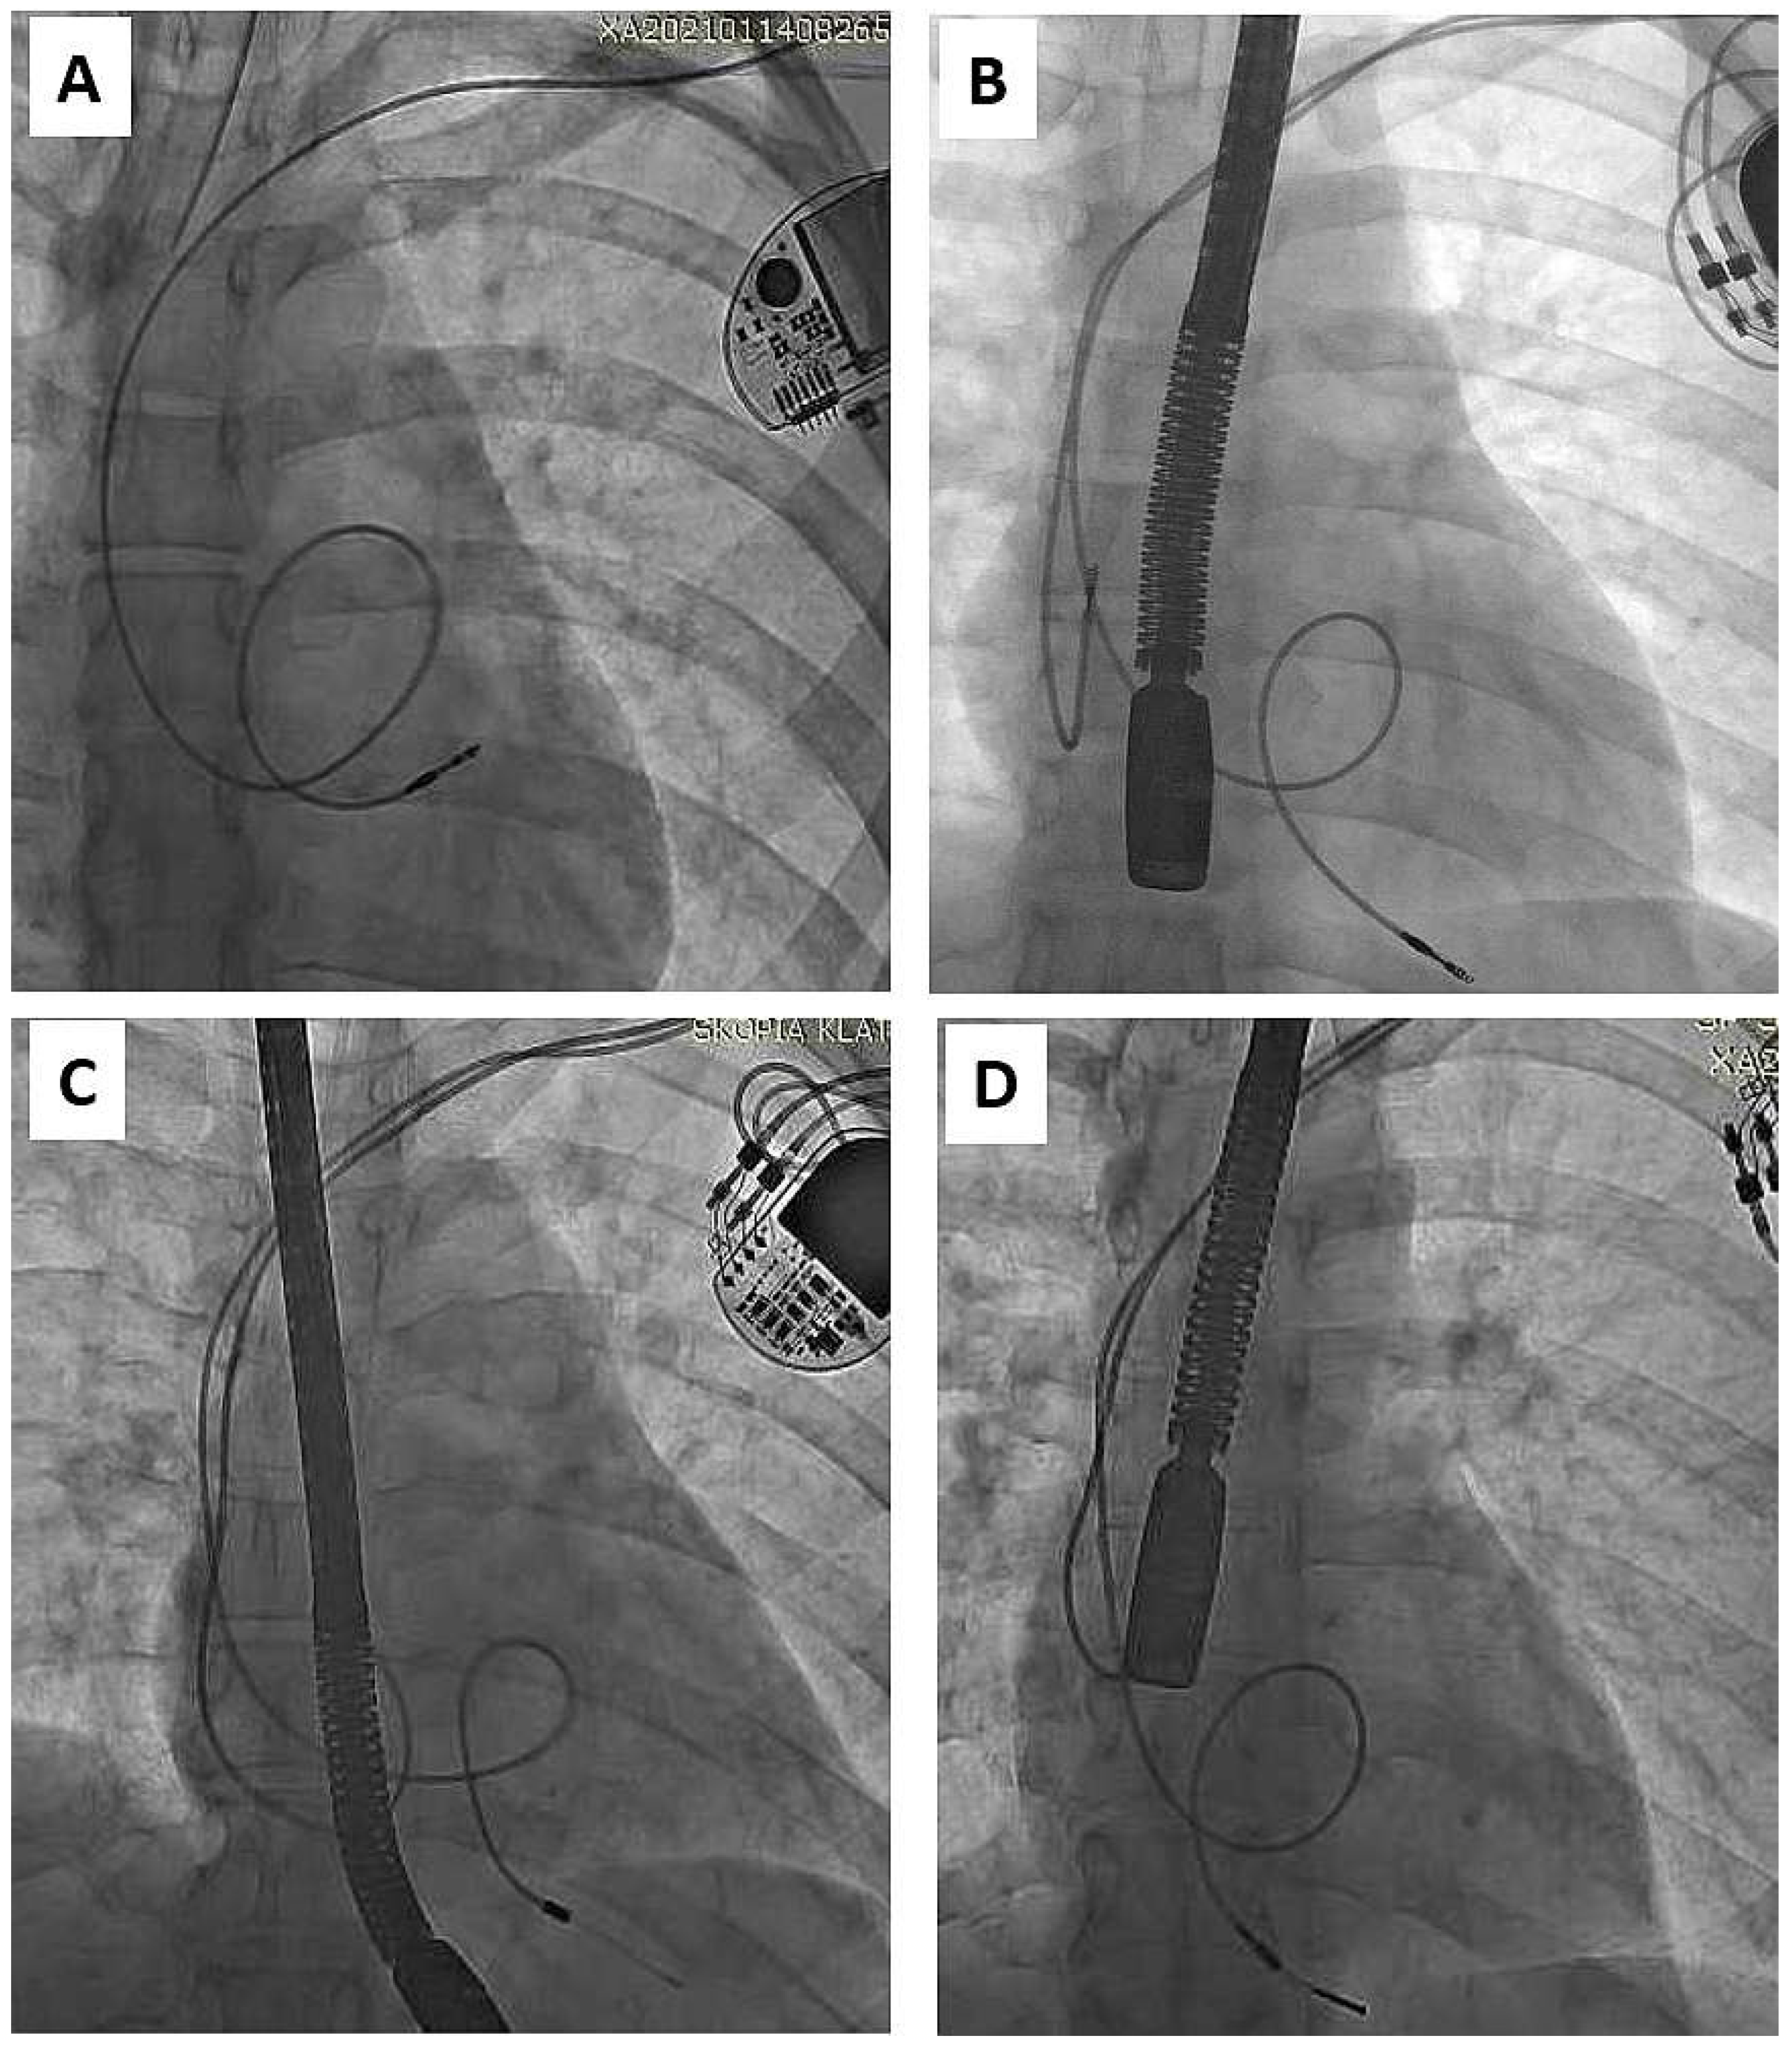

As mentioned in the Introduction Section, the problem appears when children enter adulthood with old or very old leads, if still “functional”. Adequate pacing/sensing thresholds and normal impedance levels do not guarantee long lead function in the context of body growth [3,4,5,6,7,8,33]. Such functional leads, straightened (Figure 1) or looped (Figure 2), can adhere to the heart structures [34]. The leads are covered with a thick film of fibrous, usually calcified tissue, causing additional damage to external lead insulation (by pulling out and moving through the calcified scar). Limited lead longevity, especially in children and young patients [3,4,5,6,7,8,11,12,13,14,15,16,17,18,19] creates the need for lead replacement or new lead implantation with abandonment of non-functional leads [5,11,12,13].

Figure 2.

Another trap of lead extraction in young adults—redundant lead slack (but planned) resulting in strong adherence to the heart structures (examples A–D). It increases the risk of targeted lead fracture, atrial wall rupture or injury to the tricuspid apparatus. Lead slack to allow for growth was supposed to prevent lead straightening, but his technique did not live up to expectations and was abandoned. (A) VVI pacing system. Old unnecessary (but made on purpose) lead loop located in RA and RVOT. (B) DDD pacing system. Proper atrial lead route and loop on ventricular lead finally located in RVOT. (C) DDD pacing system two leads, two loops (D) Another one DDD system. Proper atrial lead course and loop of ventricular lead finally located in RVOT. Presence of old models of passive leads indicates for more difficult extraction.